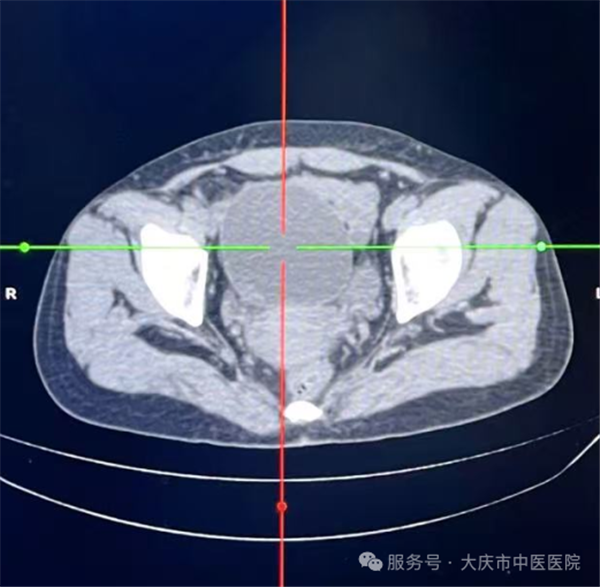

这项技术的核心优势在于“精准微创”,手术全程在超声实时监控下开展,医生通过细针经皮肤穿刺进入囊肿内部,先将囊液彻底抽出,再向囊内注入硬化剂,破坏囊肿内壁的分泌细胞,有助于降低复发风险。整个操作无需切开腹部,创伤仅为针尖大小,对周围组织影响极小。

从临床操作来看,这类手术流程规范,医护团队会严格执行无菌操作,全程监控穿刺路径与针尖位置,确保每一步操作精准可控。由于创伤极小,患者术中多无明显腹部不适感,出血量极少,整台手术耗时通常不足30分钟,能最大程度减少对正常生活工作的干扰。